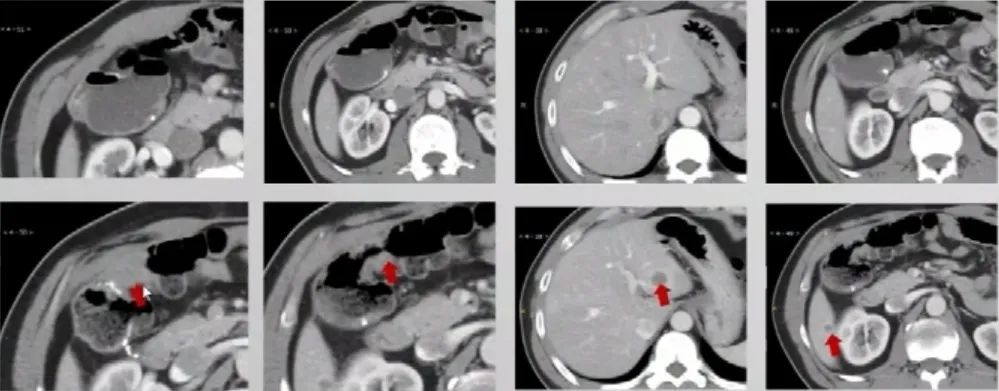

2017.11超声和CT

腹部超声:肝内多发性占位病变性质待查,结合病史考虑转移性肝癌可能,其它疾患待排,建议超声造影。

胸腹部增强CT:1.“右半结肠癌术后”,吻合口远侧复发肠癌,CT分期 rT3N0M1a;2.肝S3、S6病变,结合病史,考虑转移。

▲上:2016.12.21;下:2017.11.14。